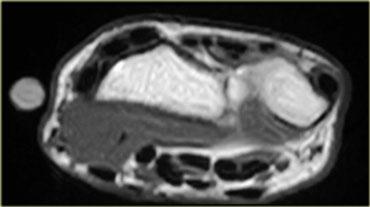

Hình bên trái là hình ảnh khảo sát cổ tay cho thấy một cơ gấp cẳng tay phụ.

Hình bên trái minh họa một cơ phụ ở mặt lưng cổ tay (trên chuỗi xung T1W và T2W).

Dưới vị trí đánh dấu là một khối bờ rõ, đồng tín hiệu với cơ bình thường.

Đây là một cơ ở mức giữa các xương cổ tay, có tín hiệu bình thường.

Thông thường, ở mức này, không có cơ nào ở phía duỗi của cổ tay, chỉ có gân.

Đây là cơ duỗi ngón tay ngắn phụ (accessory extensor digitorum manus brevis).